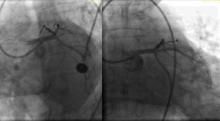

Chandan Devireddy, M.D., offers insights about what he saw as the top take aways from the 2019 Transcatheter Cardiovascular Therapeutics (TCT) annual meeting. He is cath lab director at Emory University Hospital Midtown, associate professor of medicine of interventional cardiology at Emory University, and chairperson for the Society of Cardiovascular Angiography and Interventions (SCAI) Communications Committee.

Devireddy said his key take aways from TCT 2019 were:

• The poor results of the Boston Scientific Acurate Neo self-explaining TAVR system compared to the current devices on the U.S. market;

• Results of the Abbott Portico TAVR system;

• Levant Trial shows no increased mortality due to use of a paclitaxel-coated balloon; and

• CT study of TAVR valve leaflet thrombosis.